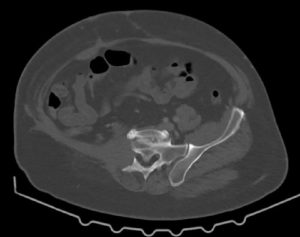

Це історія, яку неможливо забути. Молодий чоловік. Велика пухлина тазової кістки. Складна локалізація, високий ризик та мінімум шансів на просте рішення. Було проведено складну операцію – радикальне видалення пухлини з реконструкцією тазу за допомогою індивідуального 3D-друкованого імпланта. Це був шанс зберегти рух та якість життя. Через 10 місяців виникло інфікування. Довелося видалити імплант разом із кінцівкою. Але ця історія не про поразку. Пацієнт повернувся до активного життя, керує автомобілем і зараз проходить підготовку до екзопротезування. Онкохірургія – це не завжди про ідеальний сценарій, але завжди про можливість вибороти життя і рухатись далі.